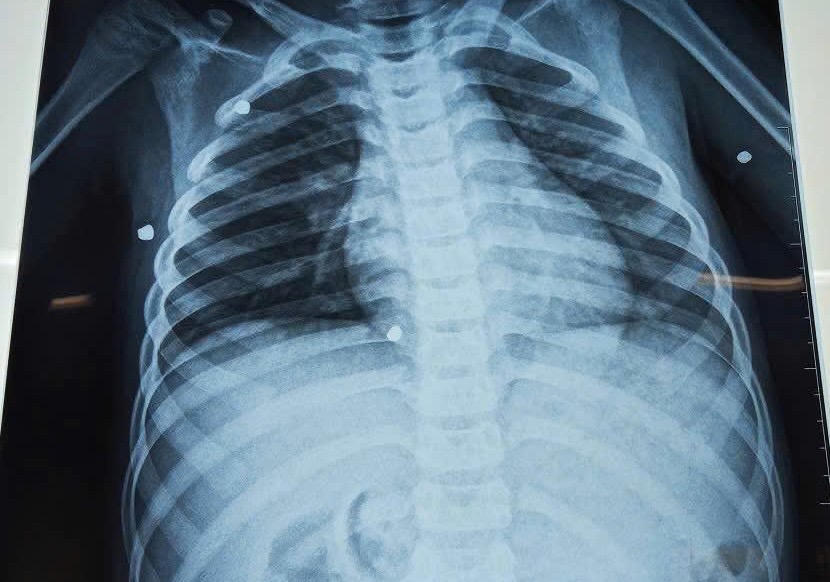

Kết quả chụp X-quang cho thấy có nhiều dị vật cản quang nằm rải rác ở nhiều vị trí trong cơ thể.

Qua thăm khám, các bác sĩ phát hiện nhiều vết thương do hỏa khí tại vùng ngực và hai tay. Kết quả chụp X-quang cho thấy có nhiều dị vật cản quang nằm rải rác ở nhiều vị trí trong cơ thể.